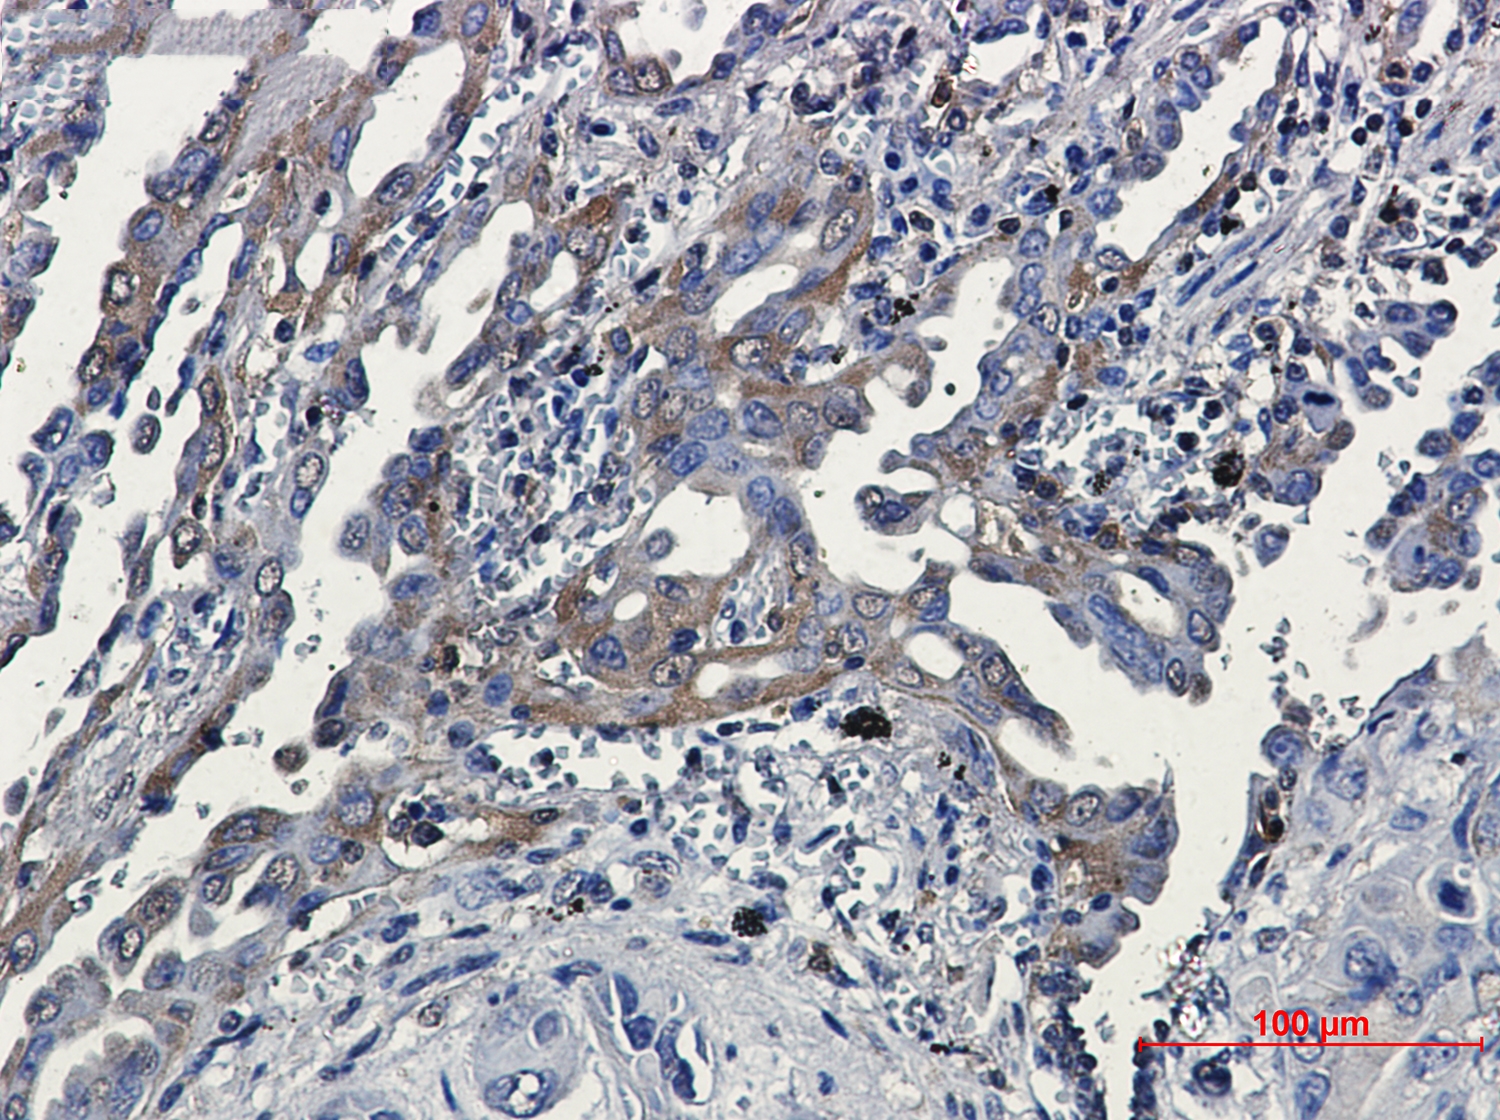

Immunohistochemical of RSK3 in Human lung cancer tissue using RSK3 antibody at dilution 1/20